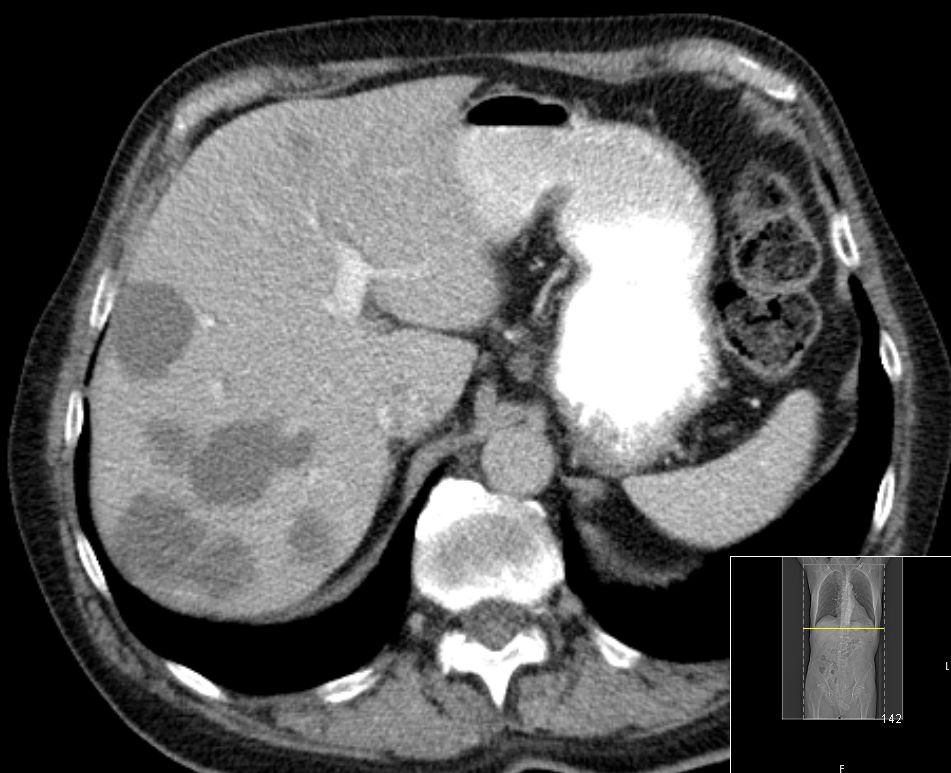

| CT | 75-jähriger Mann, der vor einem Jahr ein Rektum-Karzinom hatte: ypT3a ypN1b(2/18) Mo Li Vo G2. 5x5Gy.

Anteriore Rektumresektion, 4x 5-FU. Jetzt Lebermetastasen.

![]() |